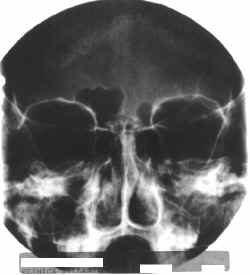

espaco2.gif (821 bytes)Ampliação da radiografia obtida da ossada e delineamento computadorizado dos restos dos seios frontais.

espaco2.gif (821 bytes)Observe a peculiar anatomia dos seios frontais com notável assimetria.

espaco2.gif (821 bytes)Processo identico ao da imagem anterior aplicado na radiografia intra-vitae.

espaco2.gif (821 bytes)Resultado apresentado no laudo de identificação cadavérica do LAF IML LR.

espaco2.gif (821 bytes)Identificação positiva.